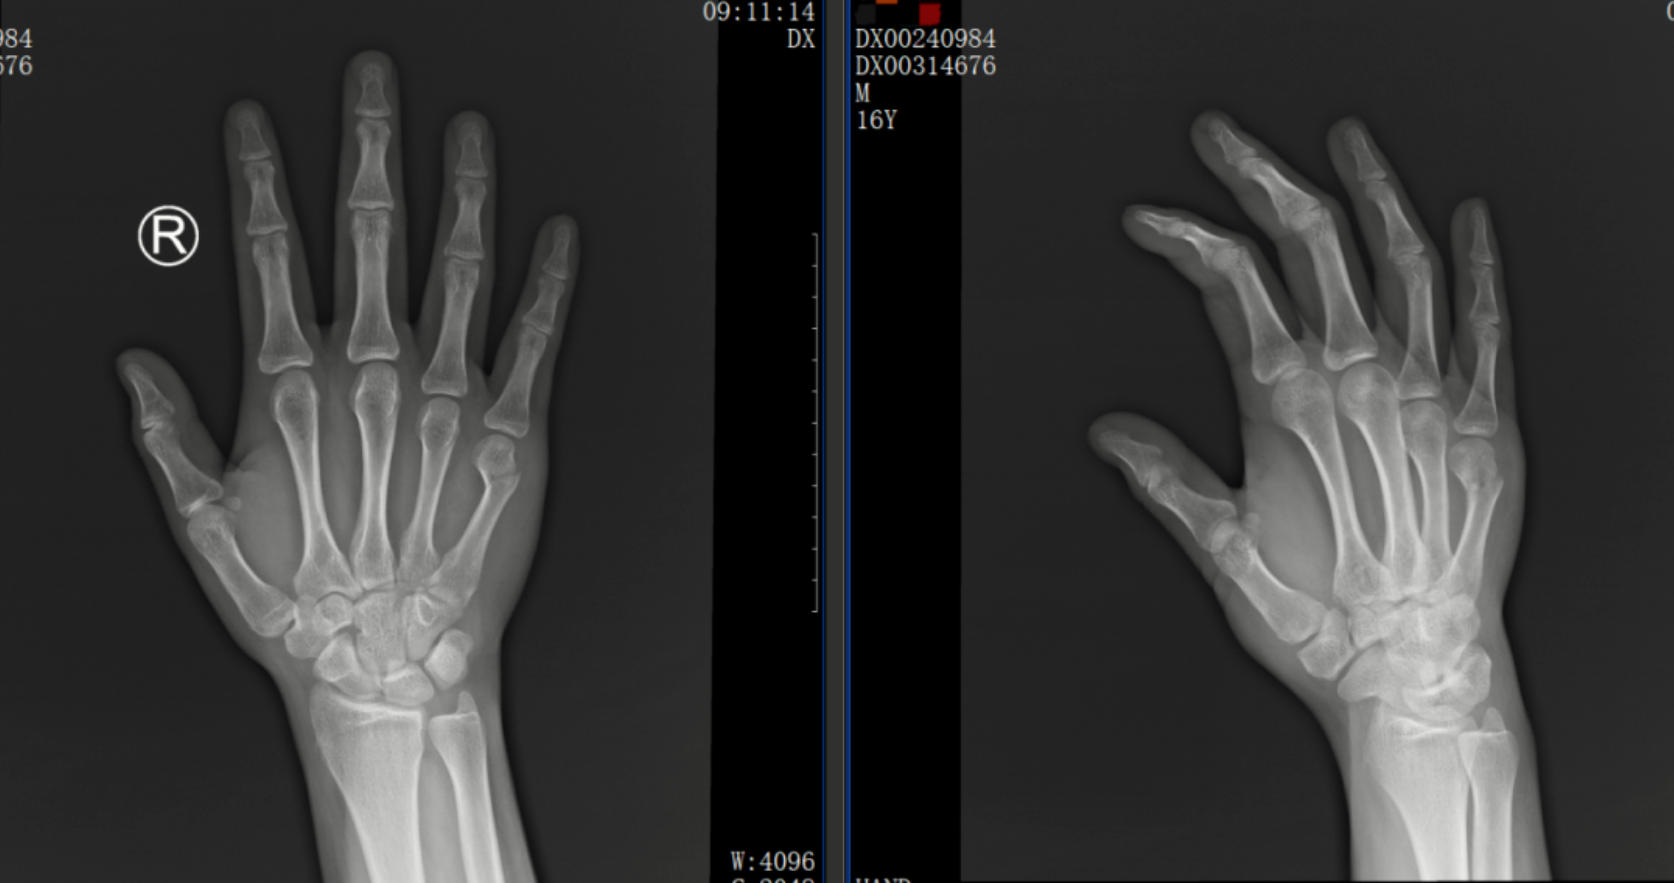

一位16歲的青少年外傷導(dǎo)致右手第五掌骨頸骨折“拳擊手”骨折,為了尋求治療來到我院,經(jīng)過我院中醫(yī)正骨中心醫(yī)師的手法復(fù)位治療,并采用杉樹皮小夾板聯(lián)合石膏固定,3周后,骨痂便順利形成,骨折愈合良好。

正骨前后影像資料